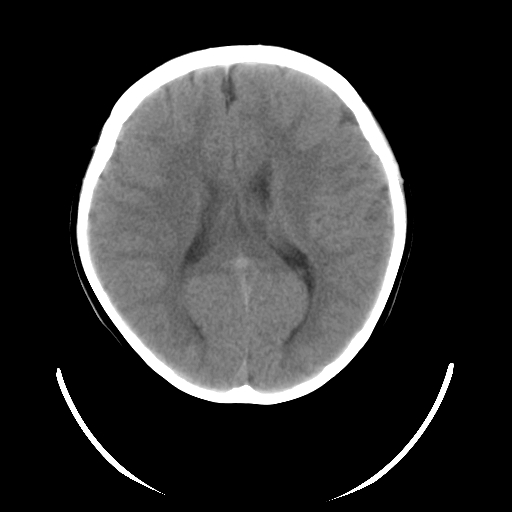

女,6岁,头痛、呕吐一天。

颅脑ct平扫未见明显异常。

头颅ct平扫未见明确异常,随诊复查。